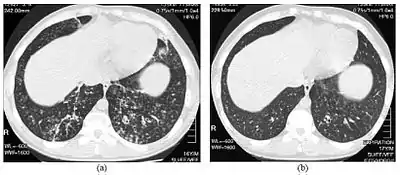

| High-resolution computed tomography images of the lower chest in a 16-year-old boy with diffuse panbronchiolitis | |

The diagnosis of DPB requires analysis of the lungs and bronchiolar tissues, which can require a lung biopsy, or the more preferred high resolution computed tomography (HRCT) scan of the lungs.[7] The diagnostic criteria include severe inflammation in all layers of the respiratory bronchioles and lung tissue lesions that appear as nodules within the terminal and respiratory bronchioles in both lungs.[4] The nodules in DPB appear as opaque lumps when viewed on X-rays of the lung, and can cause airway obstruction, which is evaluated by a pulmonary function test, or PFT.[6] Lung X-rays can also reveal dilation of the bronchiolar passages, another sign of DPB. HRCT scans often show blockages of some bronchiolar passages with mucus, which is referred to as the "tree-in-bud" pattern.[7] Hypoxemia, another sign of breathing difficulty, is revealed by measuring the oxygen and carbon dioxide content of the blood, using a blood test called arterial blood gas. Other findings observed with DPB include the proliferation of lymphocytes (white blood cells that fight infection), neutrophils, and foamy histiocytes (tissue macrophages) in the lung lining. Bacteria such as H. influenzae and P. aeruginosa are also detectable, with the latter becoming more prominent as the disease progresses.[4][5] The white blood, bacterial and other cellular content of the blood can be measured by taking a complete blood count (CBC). Elevated levels of IgG and IgA (classes of immunoglobulins) may be seen, as well as the presence of rheumatoid factor (an indicator of autoimmunity). Hemagglutination, a clumping of red blood cells in response to the presence of antibodies in the blood, may also occur. Neutrophils, beta-defensins, leukotrienes, and chemokines can also be detected in bronchoalveolar lavage fluid injected then removed from the bronchiolar airways of individuals with DPB, for evaluation.[4][9]